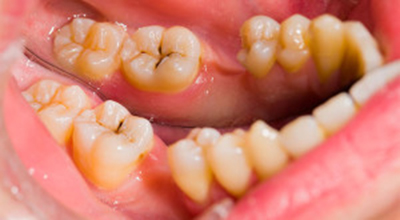

При появлении каверны усиливается чувствительность к изменению температурного режима, иногда — механического воздействия. Такие каверны, в просторечие называемые «дырками» в эмали, и становятся предметом беспокойства пациентов с больными зубами. В них начинает скапливаться еда, может появиться характерный неприятный запах.

При переходе кариеса в глубокую форму возникают кратковременные, резкие боли от разных видов воздействий. При устранении раздражителя они тоже стихают.

При появлении каверны проводится её санация различными способами удаления отмерших тканей. Затем производится пломбирование и выравнивание поверхности со шлифовкой.

Глубокие поражения, осложнённые пульпитом, требуют длительного лечения. В некоторых случаях врачу приходится удалять нерв и очищать корневой канал с последующим его пломбированием.

Одной из причин необходимости удаления может стать кариозное разрушение корня. При таком расположении сложно своевременно обратить внимание на развивающуюся патологию, поэтому часто обращение вызвано сильными болями, причина которых — пульпит.